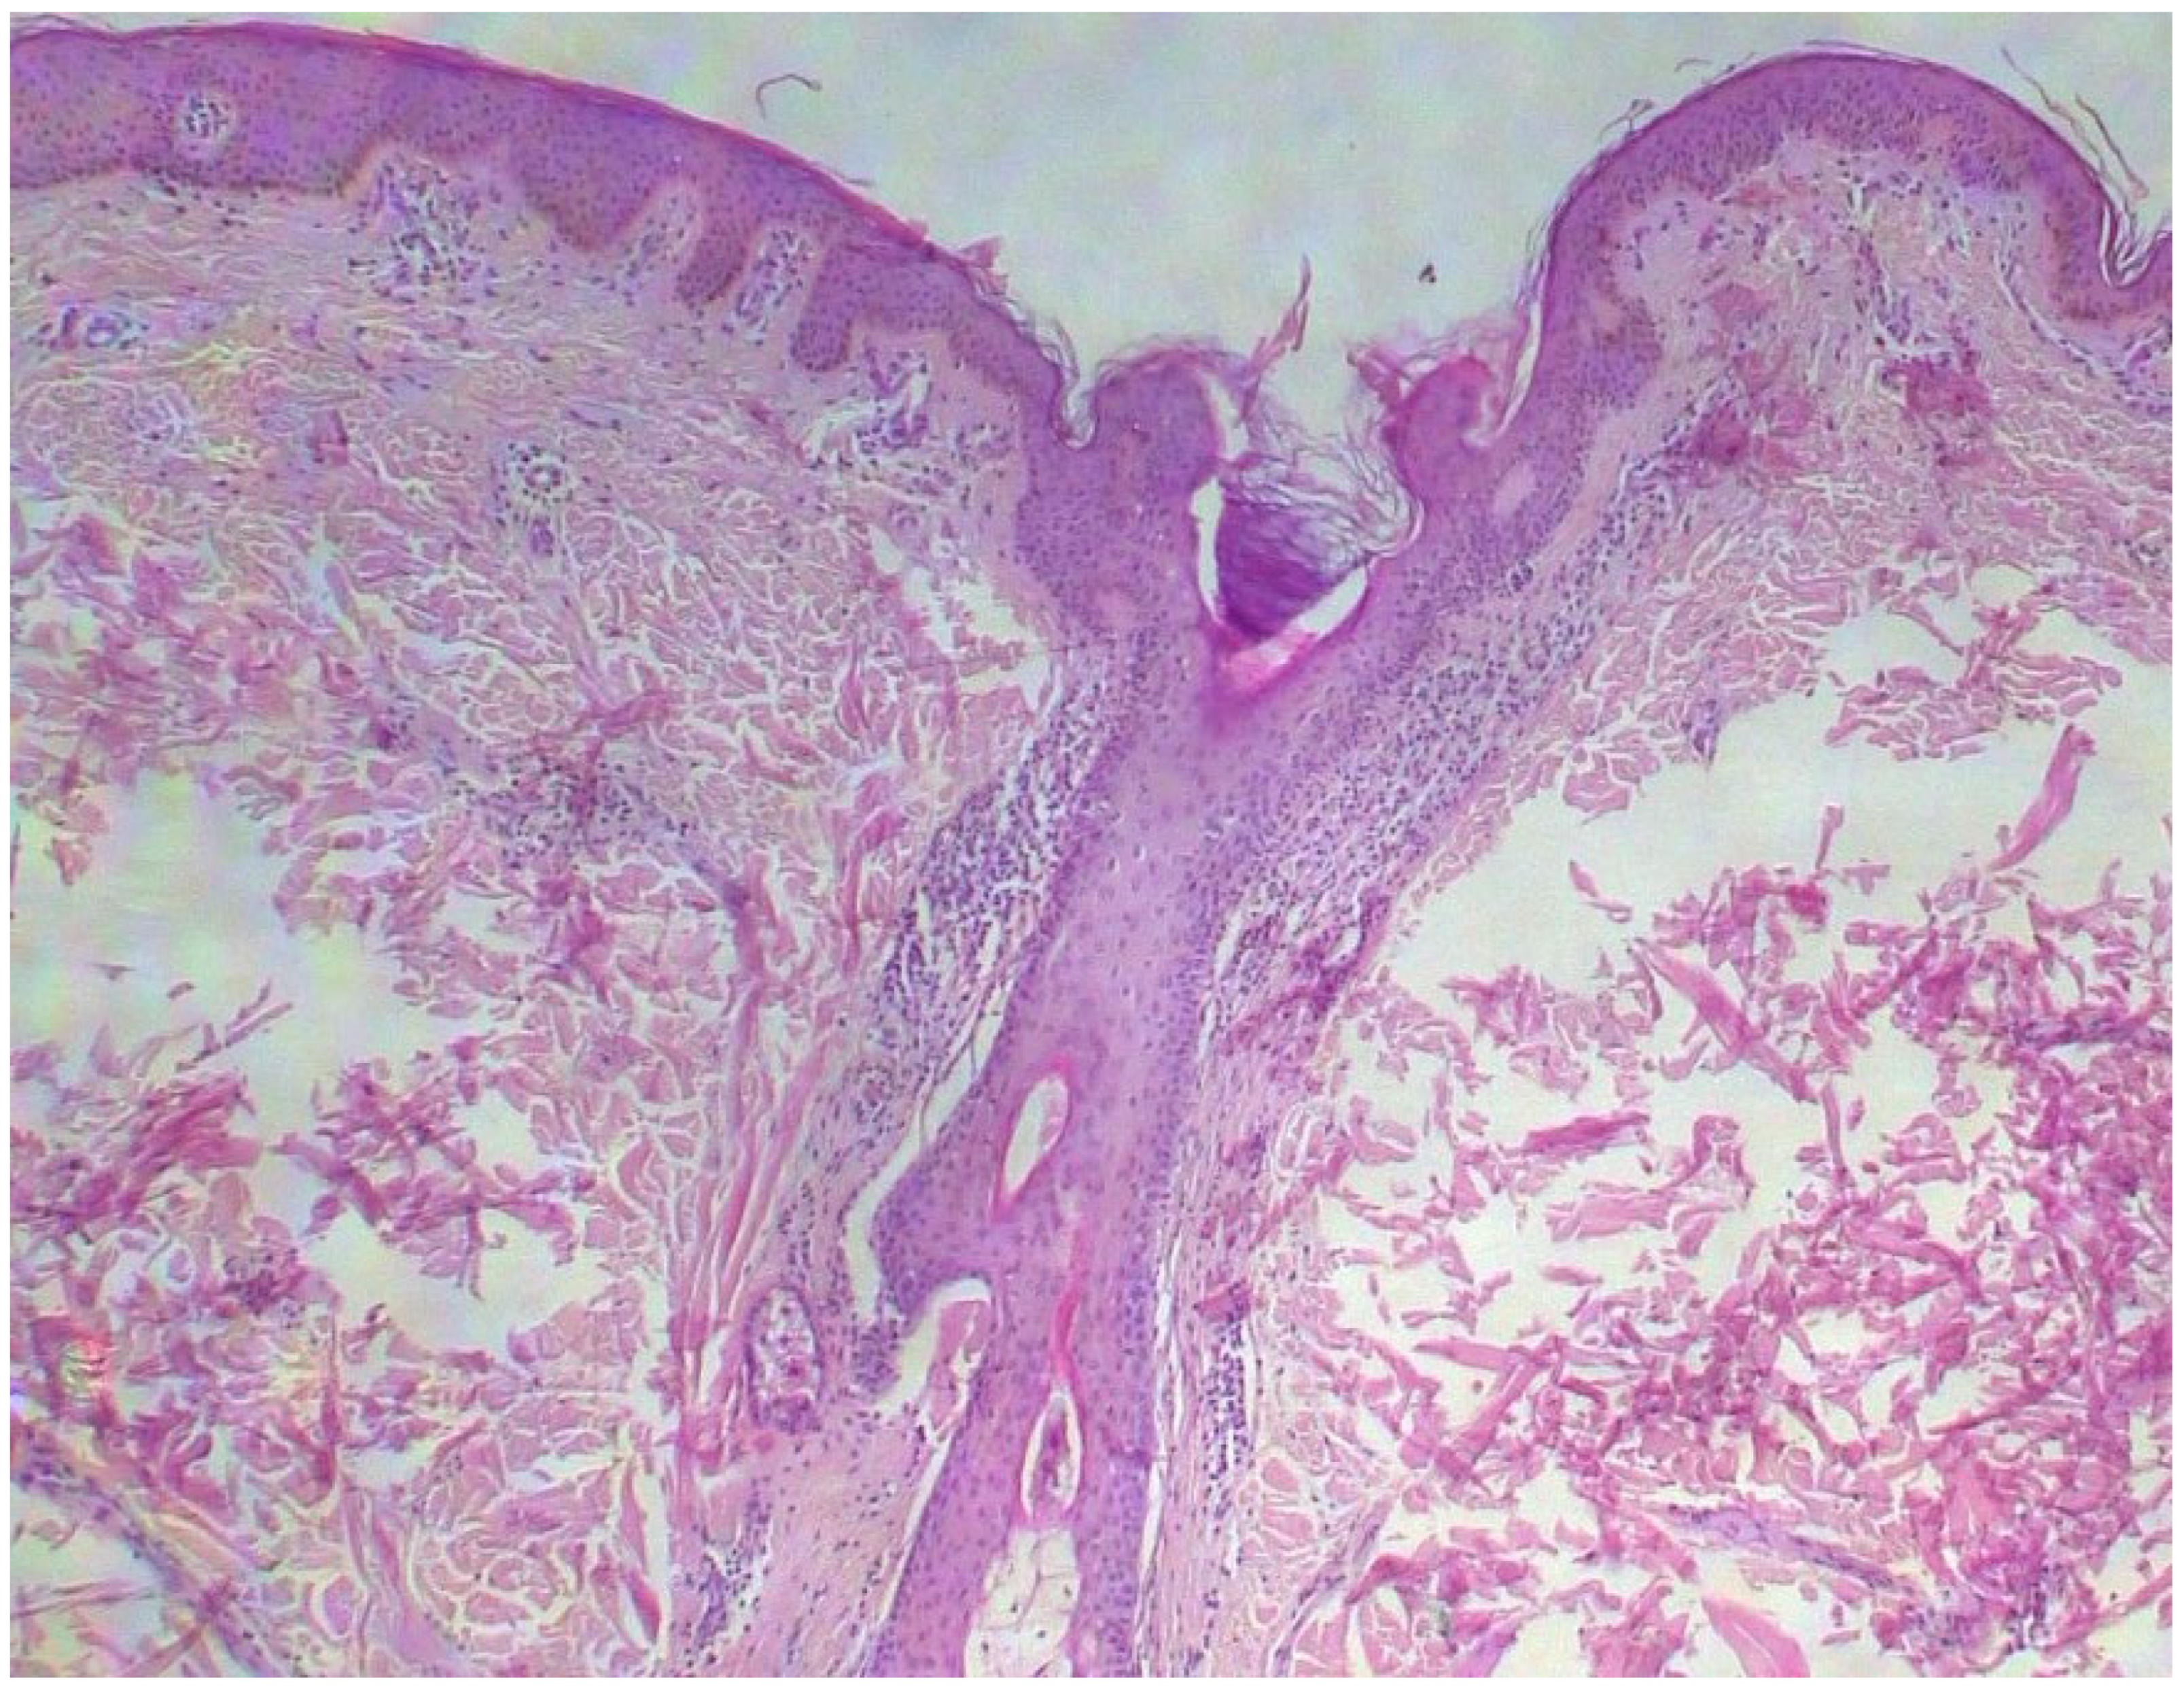

Two skin samples were taken from the upper and lower back, both showing slight, basal cell hyperpigmentation and an inflammatory infiltrate in the superficial dermis (Figure 3). Immunohistochemical stains with tryptase and CD117 showed that the infiltrate included mast cells (Figure 4), mostly with perivascular distribution. Mast cell count in six samples ranged from 11 to 12 mast cells per high-power view (CD117 and tryptase, respectively). The count per mm2 showed 34 mast cells with tryptase and 48 with CD117. C-kitD816V mutation analysis was not available. The bone scintigram did not detect any alterations and an abdominal ultrasound ruled out visceromegaly and only showed 10 mesenteric lymph nodes of non-specific appearance. He is currently under control and receiving oral levocetirizine 5 mg at night.

Figure 3. Slight basal cell hyperpigmentation and superficial inflammatory infiltrate (He, ×100).

Diagnostics 15 01370 g003

Figure 4. Mast cell infiltration (CD117, ×400).

Diagnostics 15 01370 g004